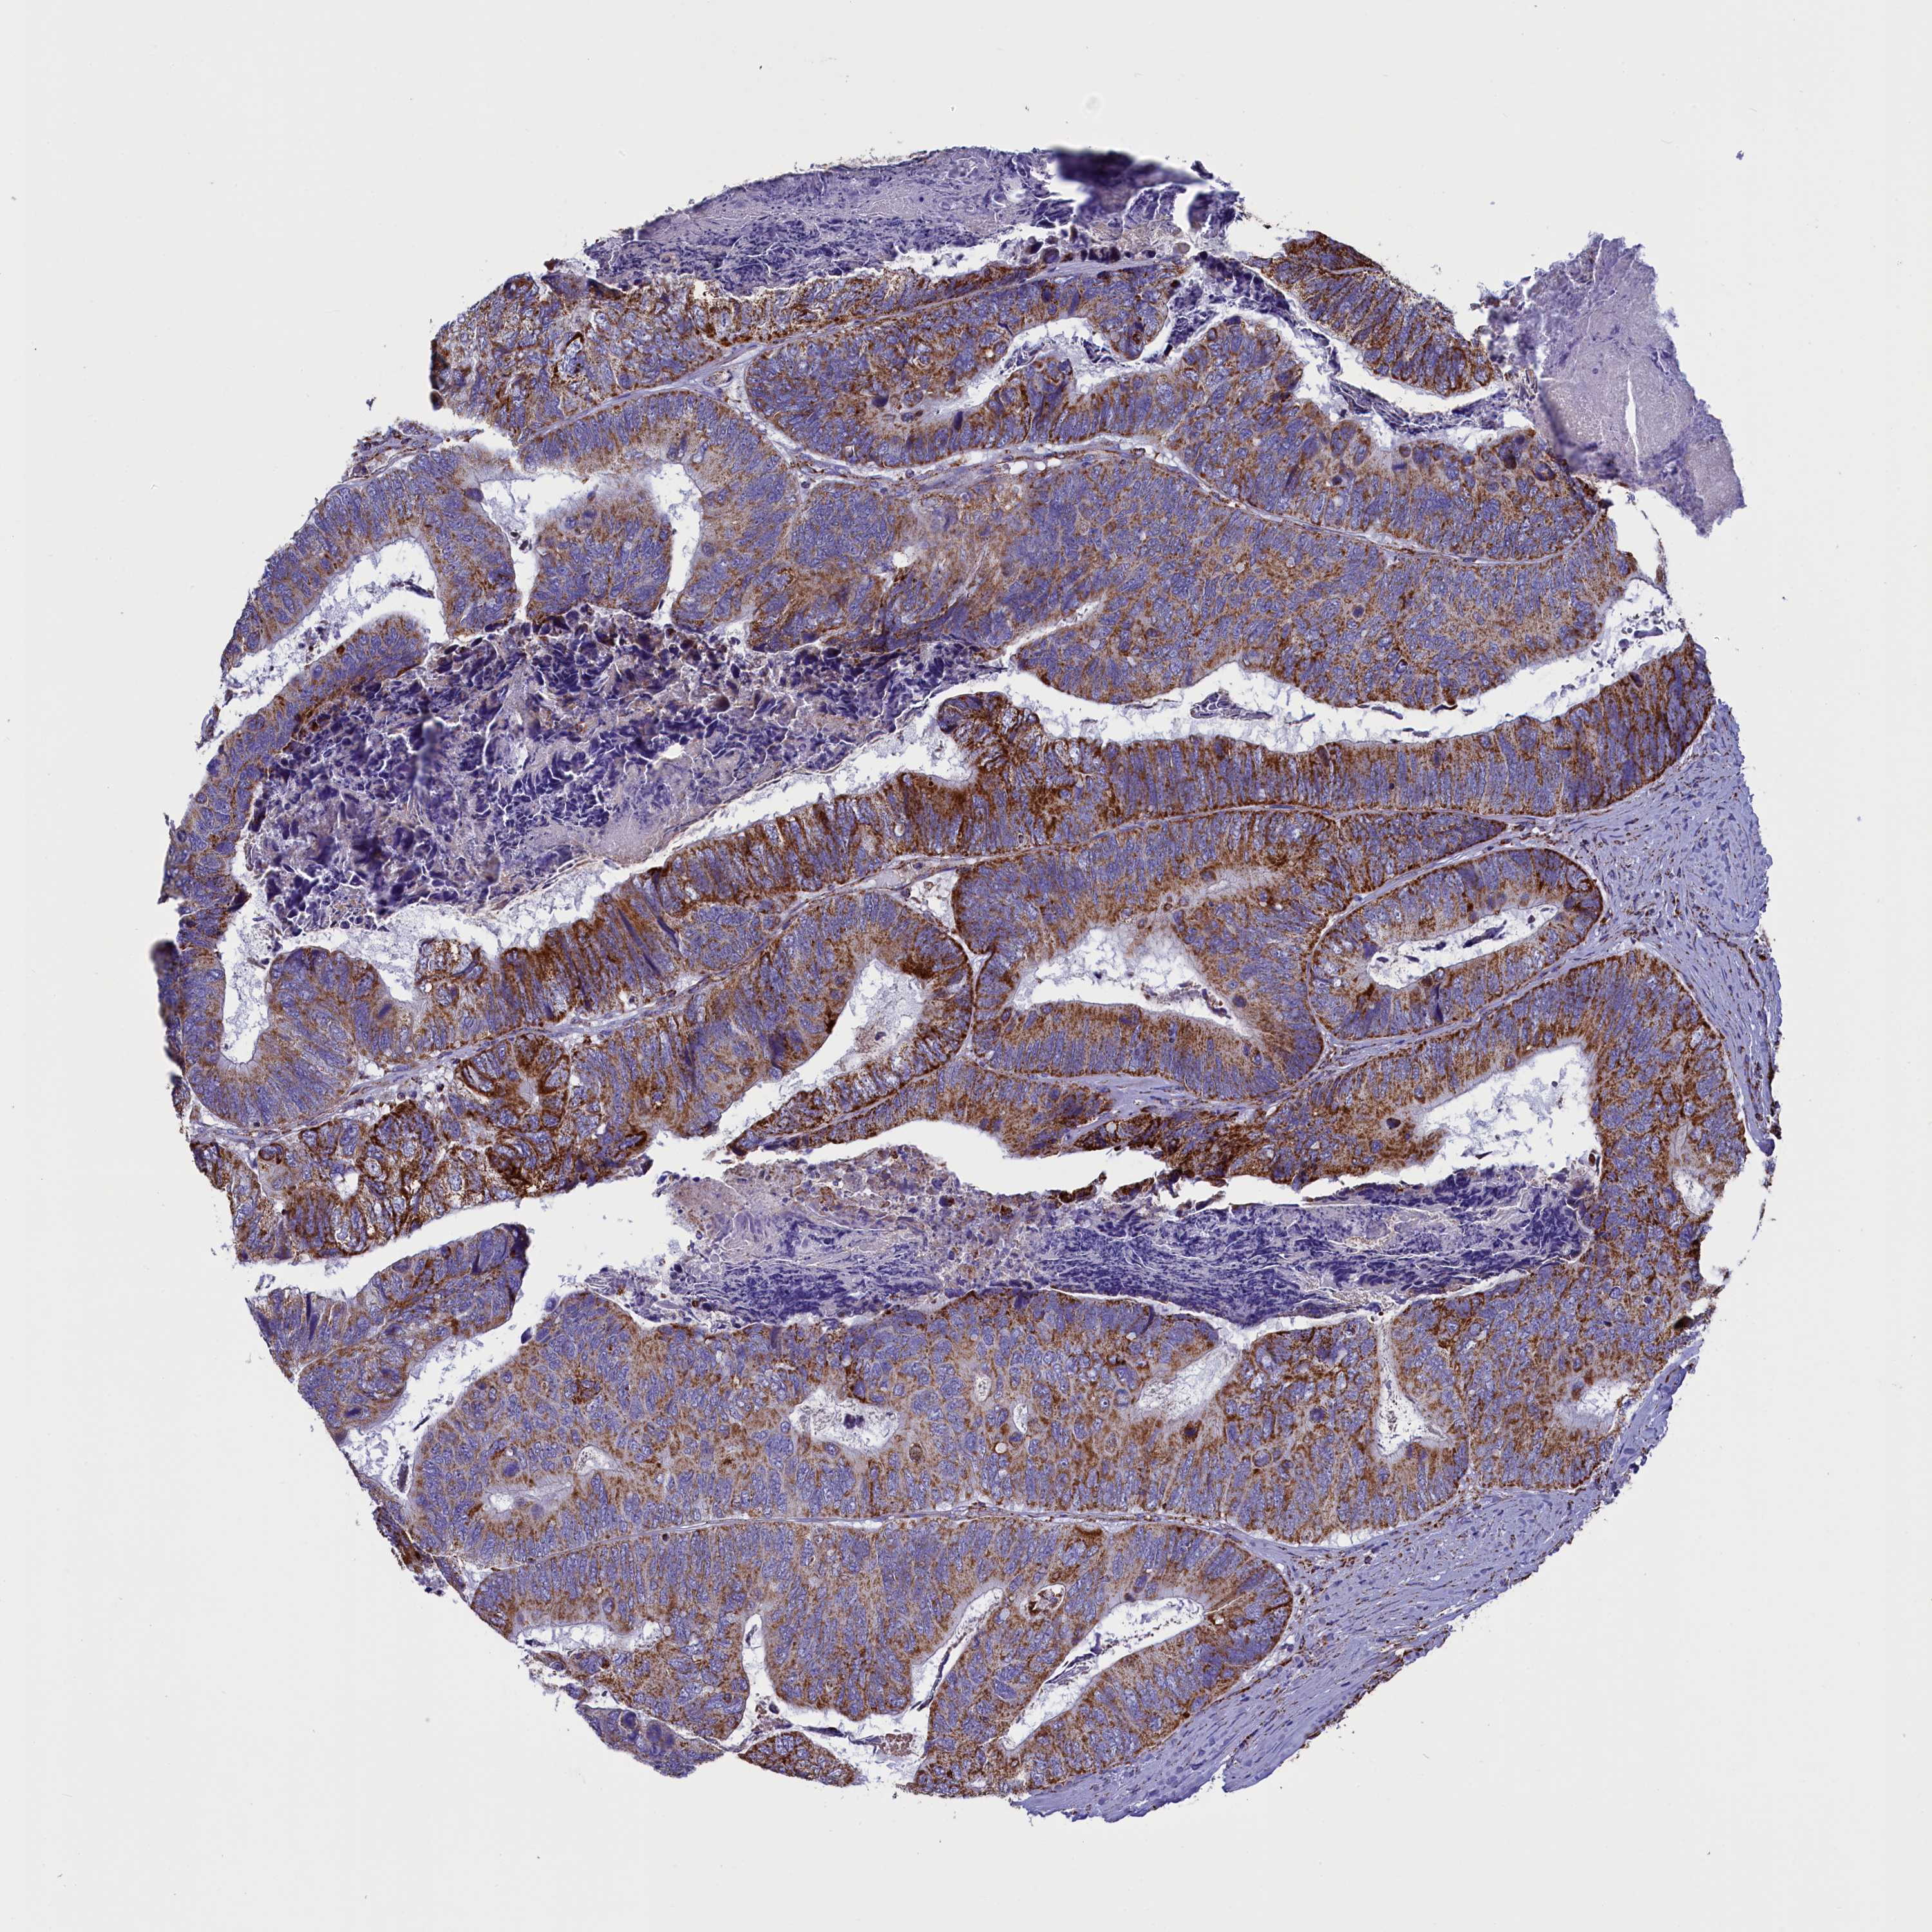

CANCER COLORECTAL CANCER Show tissue menu

Colorectal cancer

Human cancer

Colon adenocarcinoma

Rectum adenocarcinoma